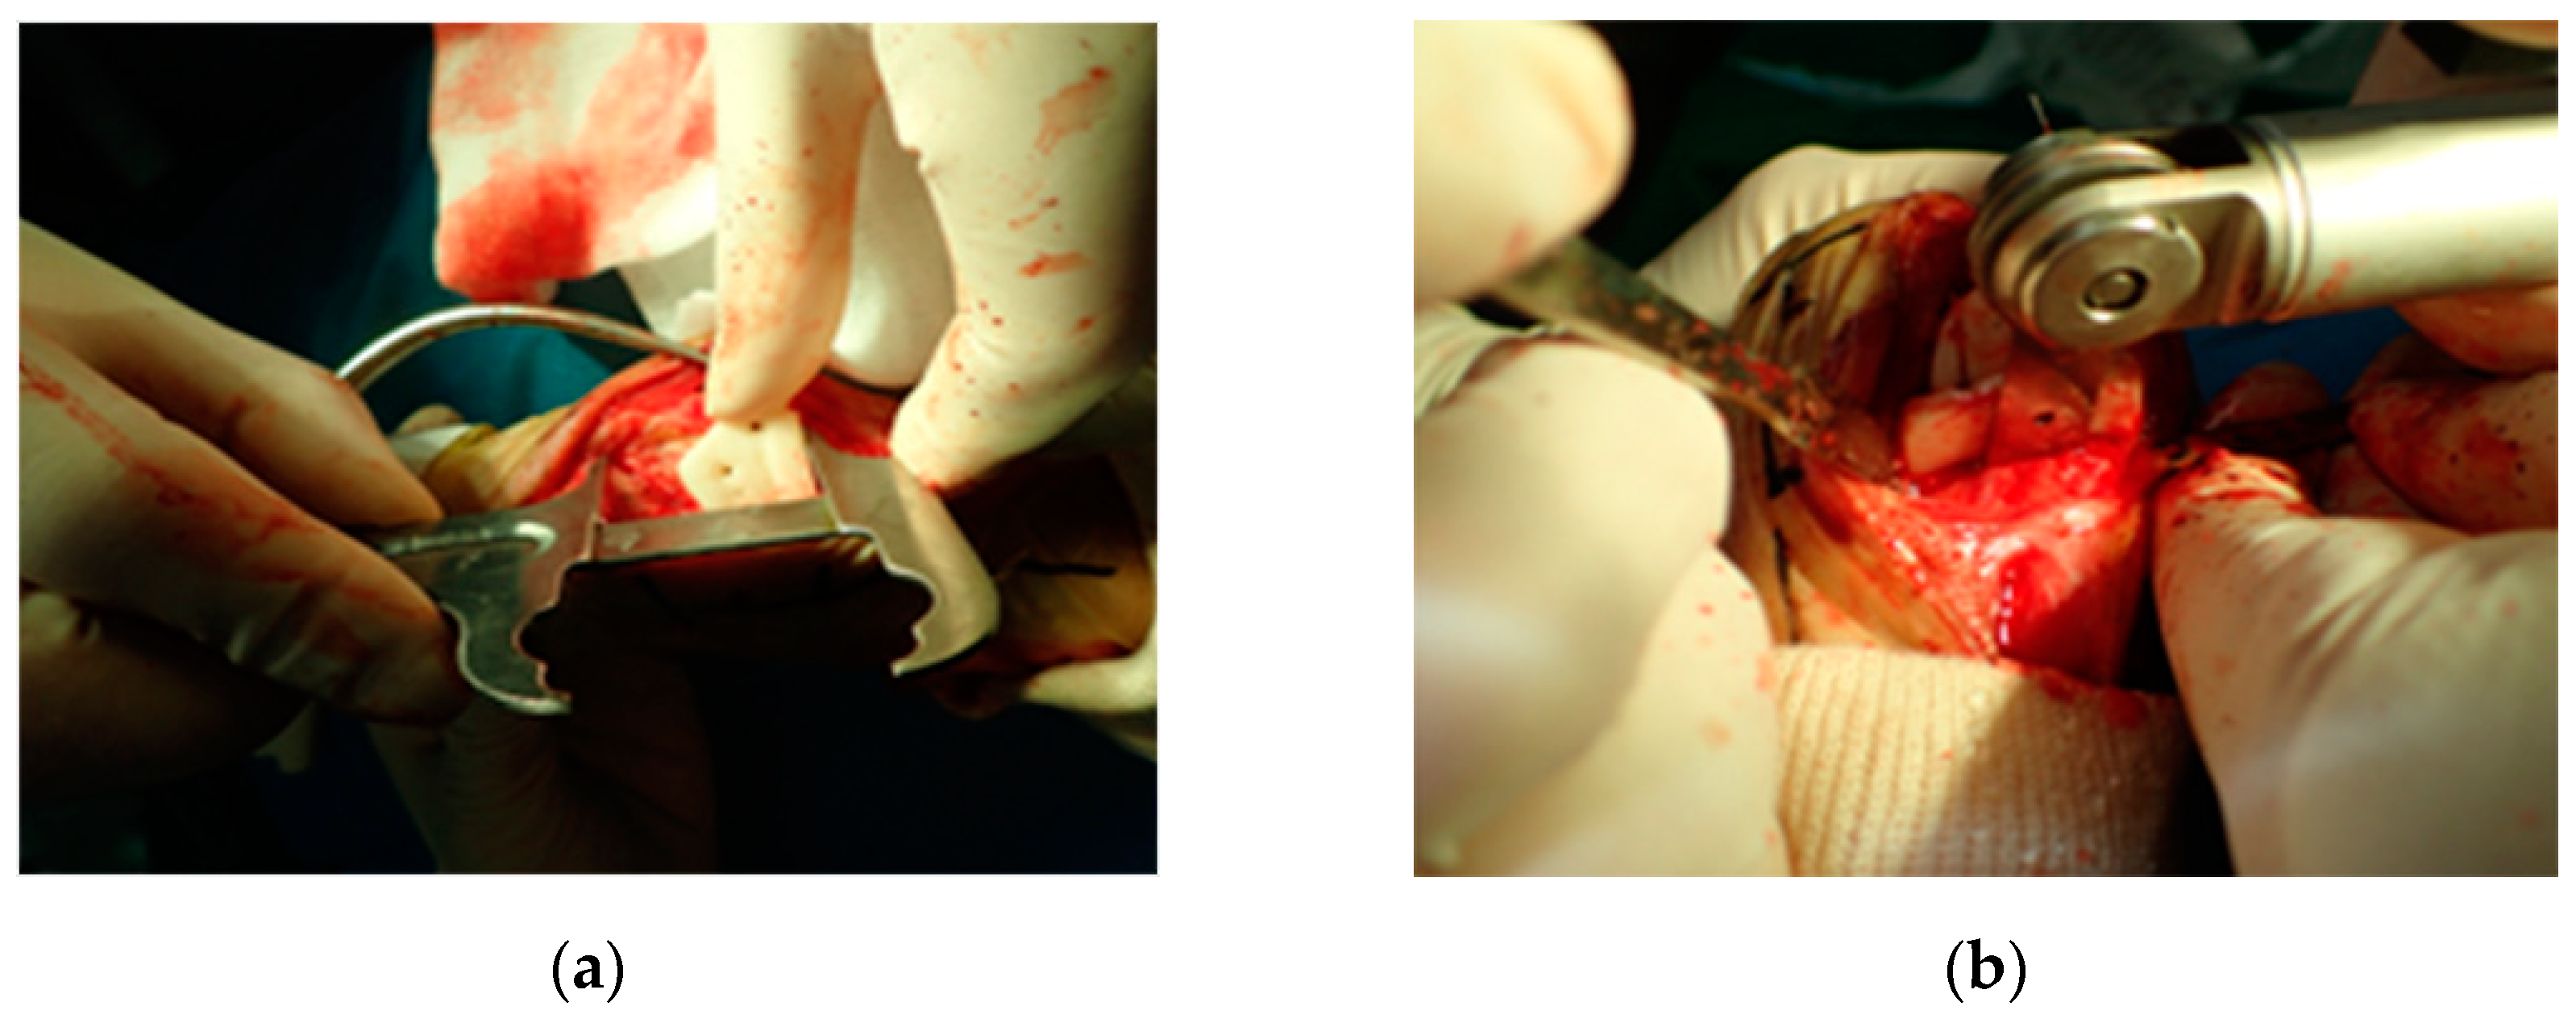

2.5. Surgery and Evaluation